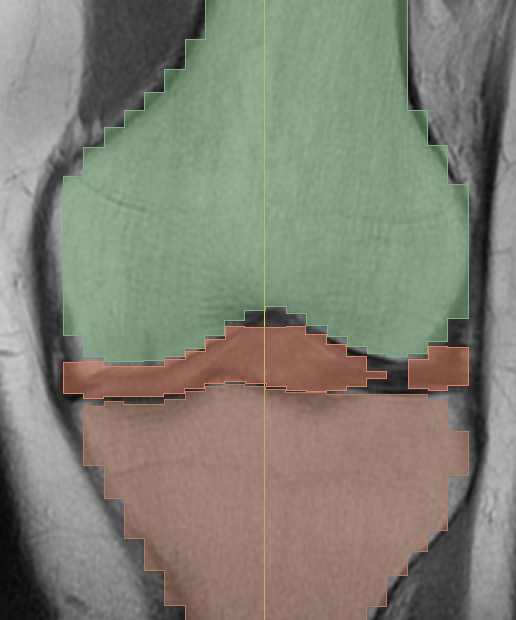

Segmentation was done in Slicer’s Segment Editor. I created separate labels for femur, tibia, and patella, plus a combined soft-tissue mask for meniscus/cartilage. Thresholding got me close; “Grow from seeds” and manual painting/erasing cleaned boundaries. I constantly compared the 3D preview with slice views to catch pinholes, jagged rims on the tibial plateau, and gaps around the patella before exporting.

Colored masks overlaid on the MRI slices. This is where errors are easiest to spot and fix.